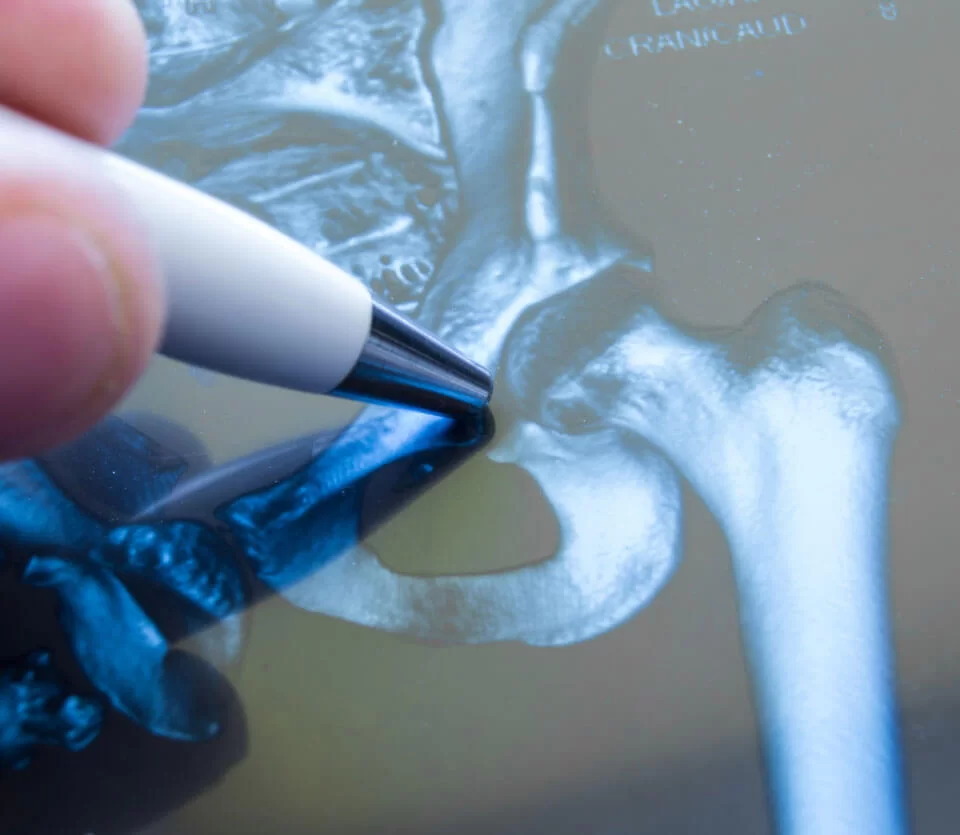

Normal hip: a ball (femoral head) and socket (acetabulum) joint. Both sides are covered with articular cartilage.

Diseased hip: osteoarthritis causes the articular cartilage to wear away, exposing bone and resulting in pain in the groin, hip, buttock or knee with restricted movement. Other inflammatory conditions like rheumatoid arthritis can also damage the hip.

Minimally invasive hip surgery: involves inserting the hip prosthesis through an incision usually <10 cm. This technique causes less muscle cutting and blood loss, giving faster recovery and a smaller scar; suitability depends on patient factors and is assessed during consultation.

Hip Anatomy and Replacement